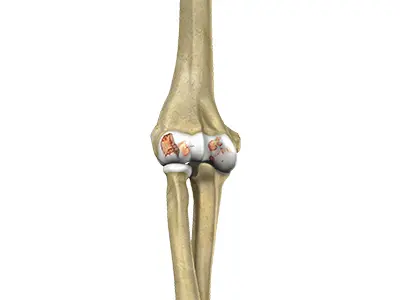

Elbow Osteoarthritis

Elbow osteoarthritis is a degenerative joint disease that affects the elbow, causing the smooth cartilage that lines the ends of the bones (humerus, radius, and ulna) to gradually wear away.